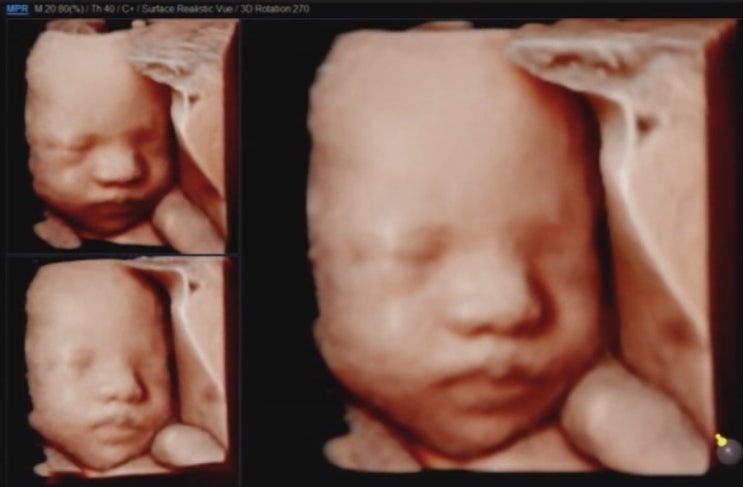

예비 달이맘_임신부터 출산 story_27주차_우리 달이 입체초음파를 보고 왔어요!

2020.5.19 Tue. 27주 4일차가 되는 날입니다! 어느 새 우리 달이 만나는 예정일도 100일이 채 남지 않았어...